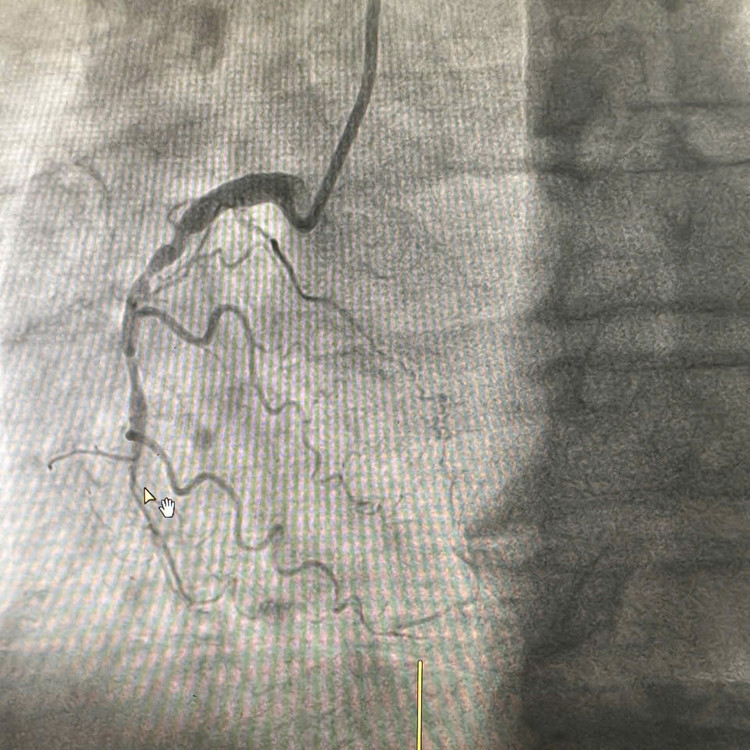

| Tắc mạch gây nhồi máu cơ tim ở bệnh nhân - Ảnh BVCC |

![]() |